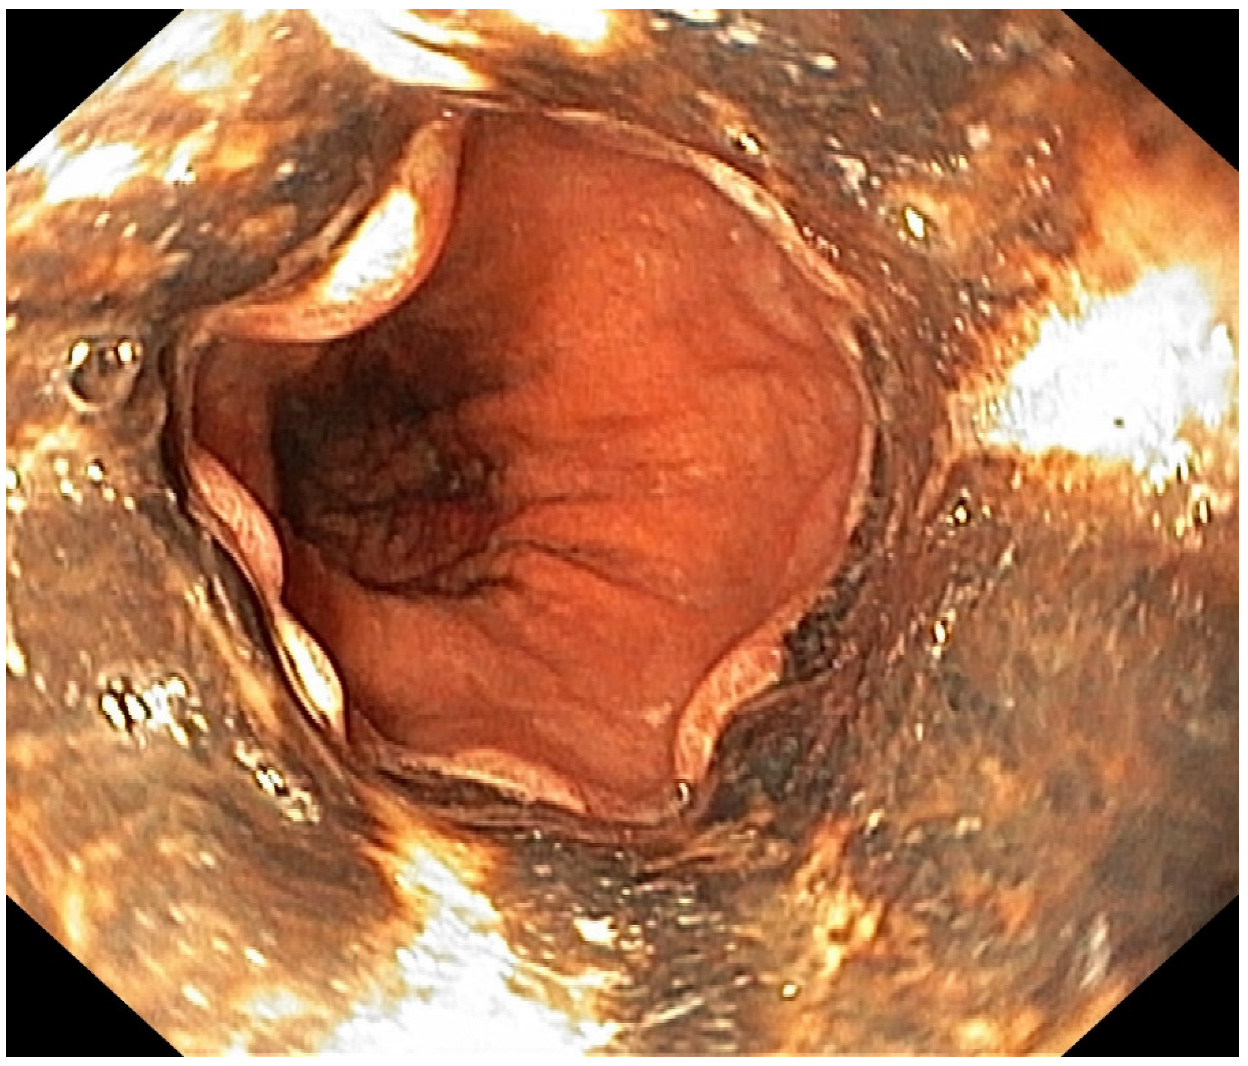

Acute Esophageal Necrosis in Acute Pancreatitis—Report of a Case and Endoscopic and Clinical Perspective

Grigore, M.; Enache, I.; Chirvase, M.; Popescu, A.L.; Ionita-Radu, F.; Jinga, M.; Bucurica, S. Acute Esophageal Necrosis in Acute Pancreatitis—Report of a Case and Endoscopic and Clinical Perspective. Diagnostics 2023, 13, 562. https://doi.org/10.3390/diagnostics13030562